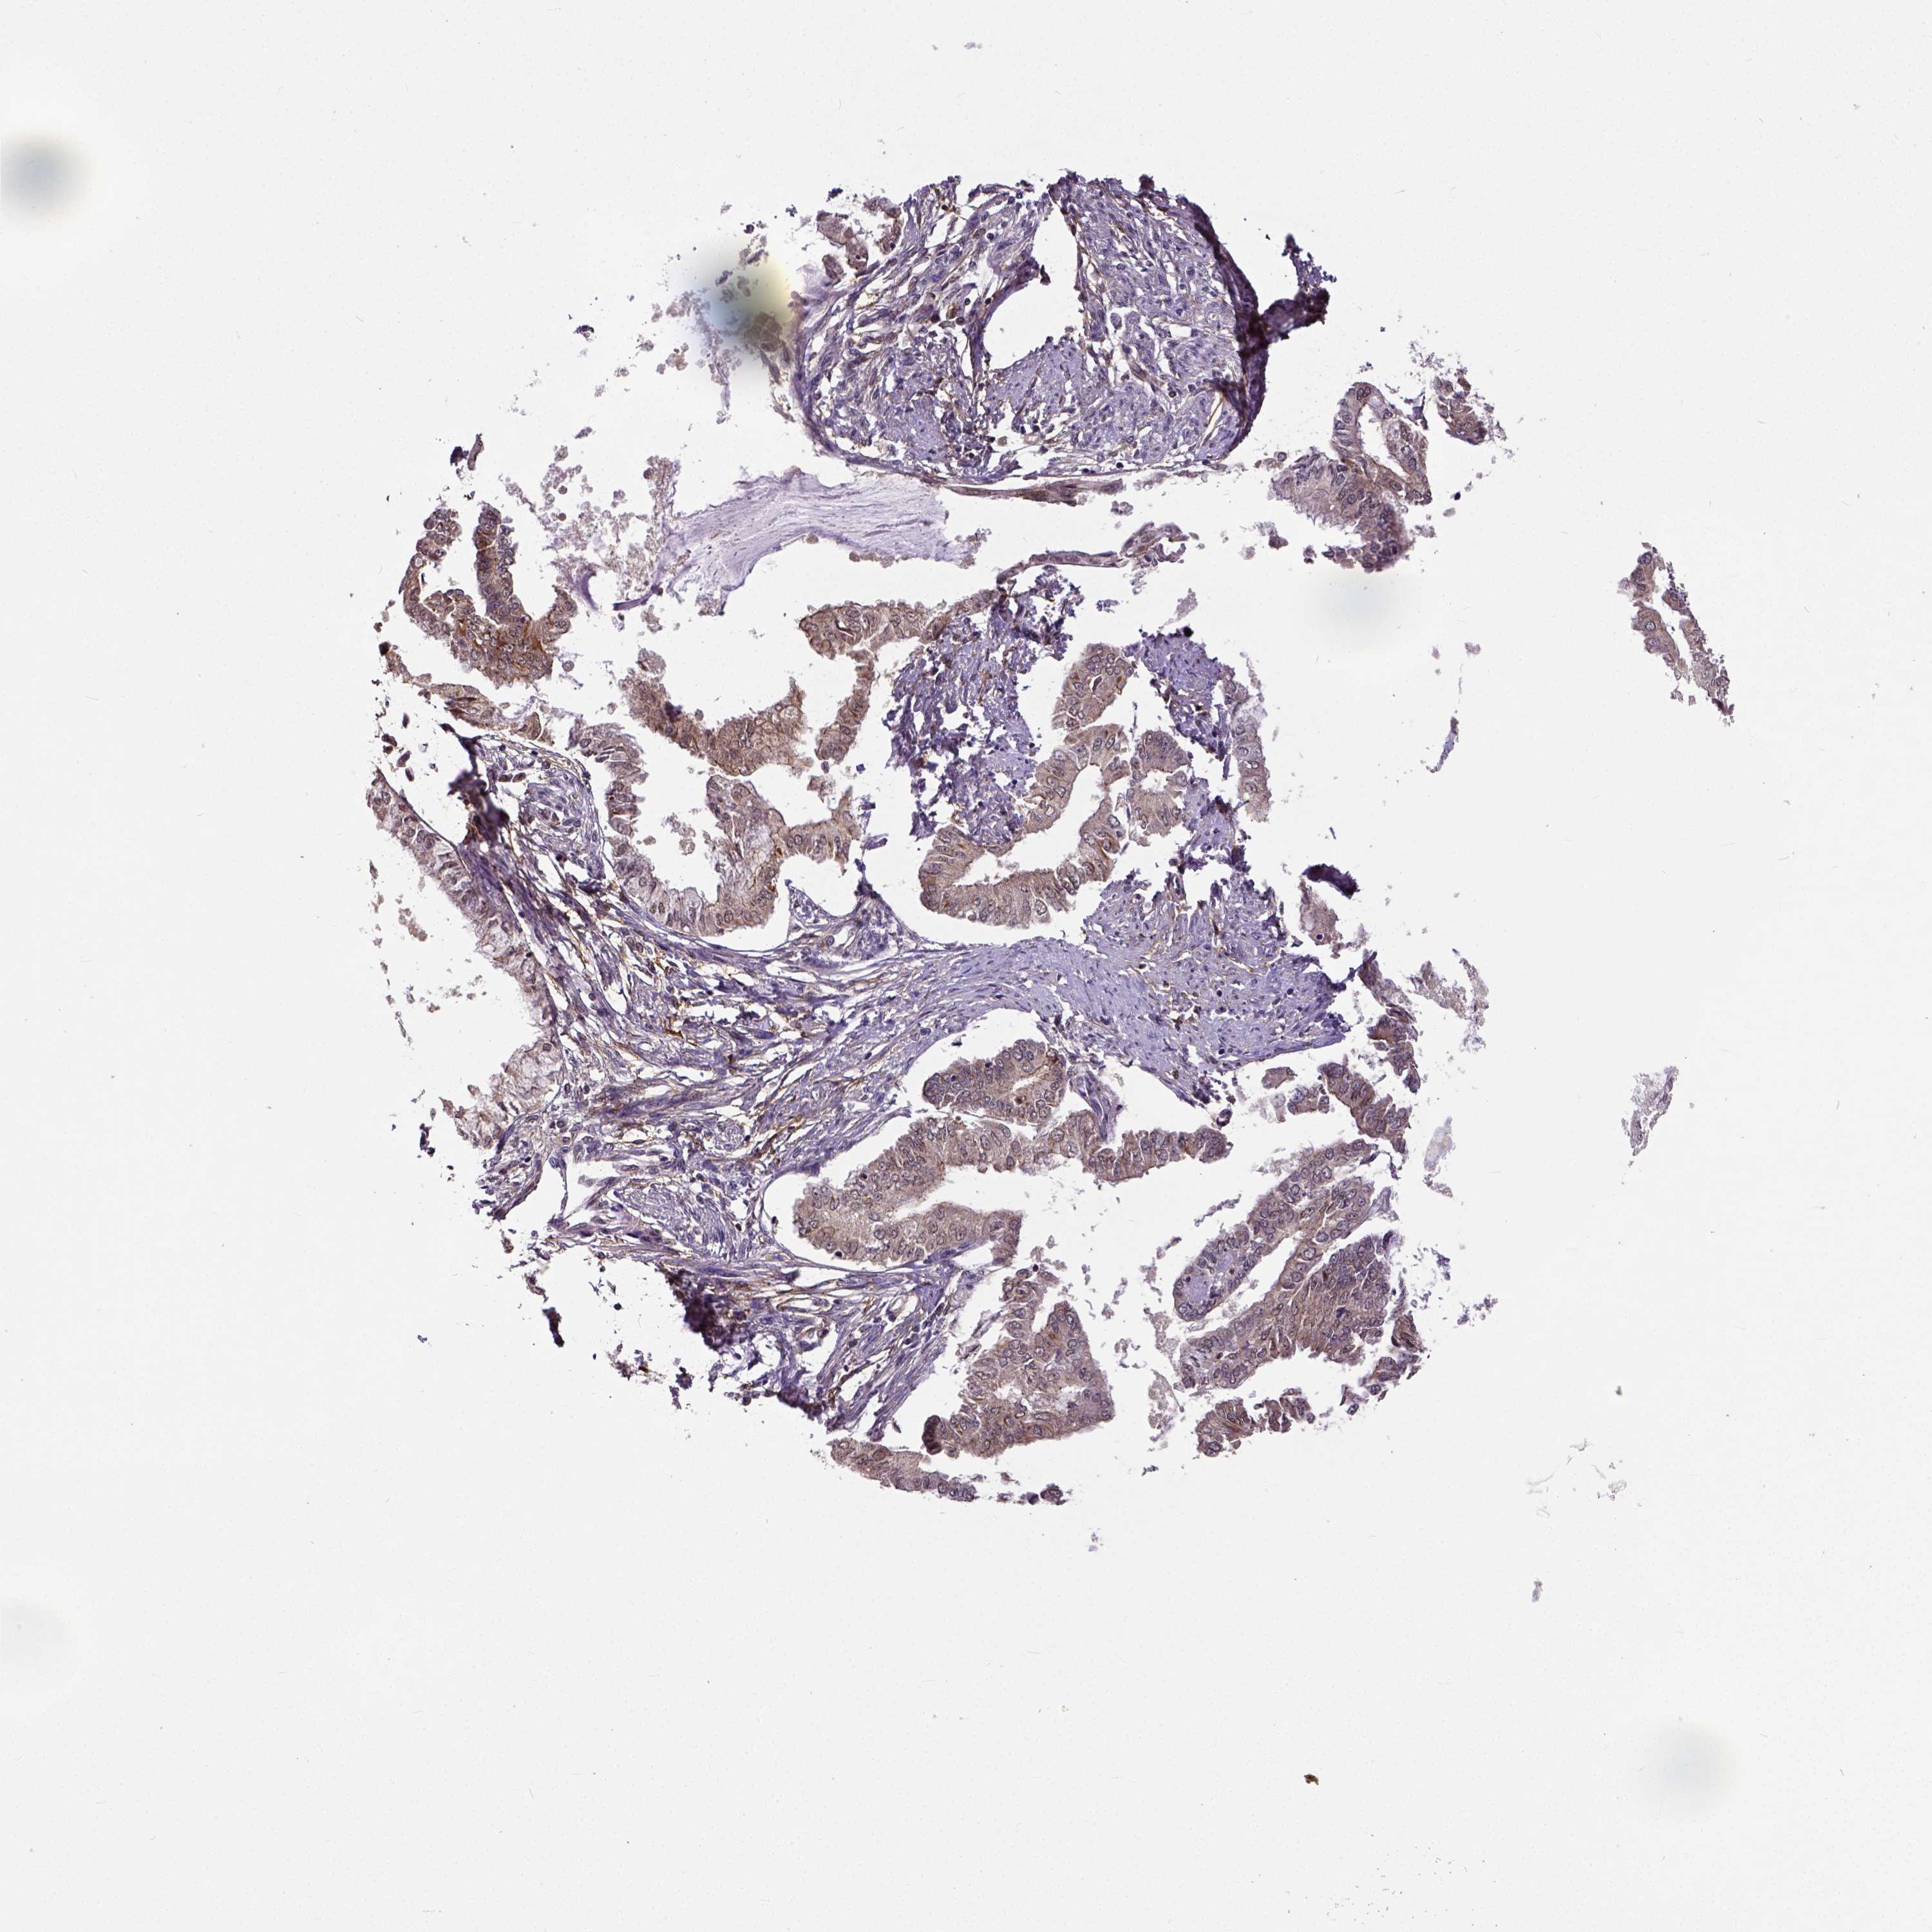

ENDOMETRIAL CANCER - Protein expressioni

A mouse-over function shows sample information and annotation data. Click on an image to view it in a full screen mode. Samples can be filtered based on level of antibody staining by selecting one or several of the following categories: high, medium, low and not detected. The assay and annotation is described here.

Note that samples used for immunohistochemistry by the Human Protein Atlas do not correspond to samples in the TCGA dataset.

Antibody stainingi

Antibody staining in the annotated cell types in the current human tissue is reported as not detected, low, medium, or high, based on conventional immunohistochemistry profiling in selected tissues. This score is based on the combination of the staining intensity and fraction of stained cells.

Each image is clickable and will lead to virtual microscopy that enables deeper exploration of all samples and also displays staining intensity scores, fraction scores and subcellular localization as well as patient and tissue information for each sample.

Antibody HPA000694

Antibody CAB068185

Staining

High

Medium

Low

Not detected

Intensity

Strong

Moderate

Weak

Negative

Quantity

>75%

75%-25%

<25%

None

Location

Nuclear

Cytoplasmic/membranous

Cytoplasmic/membranous,nuclear

Adenocarcinoma, NOS

Carcinoma, NOS